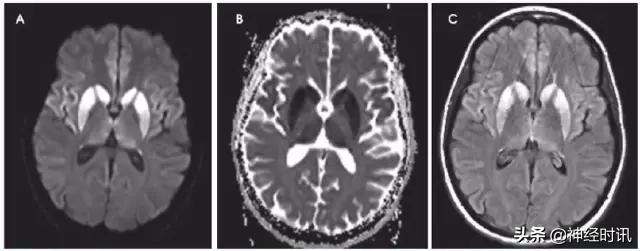

渗透性髓鞘溶解症

渗透性髓鞘溶解症最常见于低钠血症的过快纠正,也可见于营养不良、慢性酒精中毒、渗透压升高,例如高血糖和肝移植患者。典型表现为假性球麻痹和痉挛性四肢瘫,可出现桥脑中央和/或桥外髓鞘溶解(图13)。桥脑病灶位于中央,皮质脊髓束保留。桥外病变对称性累及丘脑、基底节和双侧膝状体和大脑白质。T2高信号的出现可能滞后2周,但弥散受限出现于24小时内,并持续达3周。弥散受限的机制尚未完全阐述,可能与细胞外的水向细胞内转移或髓鞘内分裂、空泡化,或髓鞘由于渗透作用破裂有关。

图13 一例46岁嗜酒男性,伴严重低钠血症,在纠正低钠血症后出现癫痫发作和吞咽困难。MRI显示脑桥中央部、双侧壳核、尾状核、丘脑外囊T2高信号(A&B:FLAIR),脑桥周围部和皮质脊髓束未受累。结果符合脑桥中央和桥外髓鞘溶解。